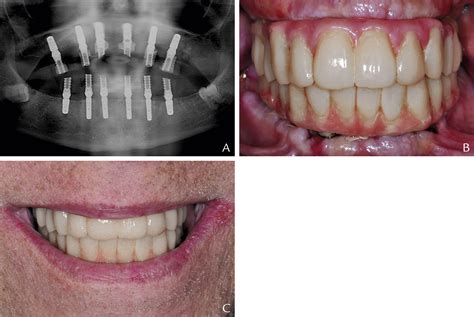

Implant Supported Prosthesis and All-on-4

The All-on-4 technique is a popular method for placing implant-supported prostheses, particularly for patients who need to replace all of their teeth in the upper or lower jaw. This technique involves placing four implants at strategic angles to maximize stability and support for the prosthesis.

The All-on-4 technique offers several advantages, including:

• Reduced Treatment Time: The All-on-4 technique can often be completed in a single day, allowing patients to leave the dental office with a fully functional set of teeth.

• Minimally Invasive: The technique requires fewer implants and less bone grafting, making it a less invasive option.

• Immediate Function: Patients can begin using their new teeth immediately, improving oral function and quality of life.

The All-on-4 technique is particularly beneficial for patients who have experienced significant bone loss and may not be good candidates for traditional implant-supported prostheses.